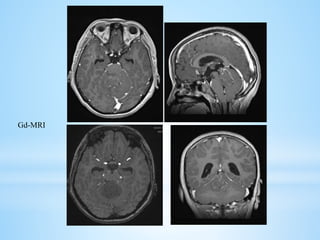

 MRI: There is a high degree of variability of MR appearances of medulloblastoma.

 T1 sequences are usually iso-hypointense to white matter and hyperintense on T2

sequences.

 Tumor enhancement can be both homogeneous or heterogeneous.

 Similar to ependymoma, approximately14% of medulloblastomas may show foraminal

extension.

 Banana sign (4th vent drapes around medulloblastoma unlike ependymoma where tumor

encroach 4th vent)

 HCP: 85-90%

Gd-MRI